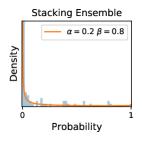

5.1 Distribution of Uncertainty Scores

Distribution of Uncertainty Scores Across Different Severity Levels As explained in Section 3, each uncertainty metric essentially defines an order/ranking among the data points. We conducted an analysis to better understand what data will be assigned high uncertainty under a particular uncertainty metric . Picking out the highest ranked data points (), we calculated the ratio of data points from each SL. Figure 4 summarizes the results as box plots for the Kaggle-DR and the Messidor-2 datasets; additional detailed statistics can be found in Table S.1 in the supplementary materials. From the plot and table, SL1 & SL2 examples account for a higher proportion among the top-ranked uncertain examples across the three ensemble methods. This finding matches our intuition that incipient disease examples (SL1 & SL2) are more likely to be considered uncertain by ensemble methods due to their ambiguity.

In contrast, the MC-dropout method showed the worst overall performance among the three, as it can be seen from the high ratios of SL0 examples among the uncertain negatives in Figure 4. The histograms in Figure 2 provides another perspective to look into the phenomenon, where a decent proportion of MC-dropout model’s predictions on SL0 inputs entailed low confidence (far from 0 or 1), which from another angle explained why MC-dropout was less specific in terms of lower FNP; many no-DR inputs (i.e. SL0) were erroneously assigned high uncertainty by MC-dropout models.

It is still an open question why the evaluated MC-dropout networks signaled relatively high uncertainty on SL0 & SL3 & SL4 data that are less likely to be ambiguous. We conjecture that much of the “uncertainty” indicated by disagreement among test-time dropout samples actually reflects the stochastic nature of dropout networks rather than the real decision uncertainty associated with the data. It is worth noting that the MC-dropout model we evaluated was not weak per se; they all achieved above Area Under Curve (AUC) scores on test sets. The weakness of individual test-time samples (which explains their low-confidence predictions on SL0 & SL3 & SL4) might have been hidden when they are aggregated into an ensemble—a well-known advantage of ensemble learning. Our results suggested that the uncertainty information given by implicit ensemble methods such as MC-dropout and TTA might not be as reliable as that from explicit ensemble approaches (e.g., stacking ensembles). Similar findings on MC-dropout can be found in some previous papers [1].